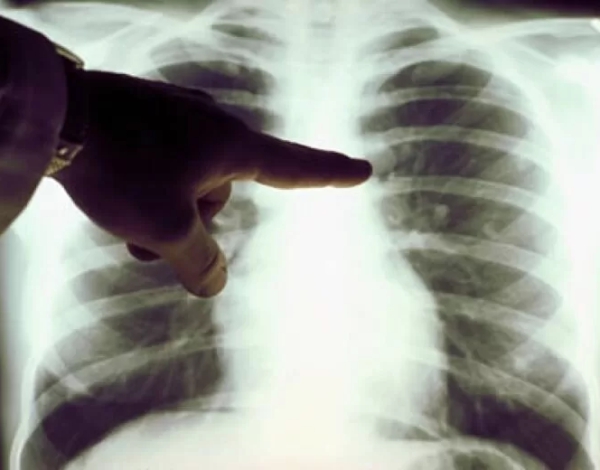

El cáncer de pulmón es un cáncer que se forma en los tejidos del pulmón, generalmente en las células que recubren las vías respiratorias. Es la principal causa de muerte por cáncer tanto en hombres como en mujeres.

Cirugía para cáncer de pulmón menos invasiva

El cáncer de pulmón y las nuevas técnicas menos invasivas son actualmente recomendadas y más seguras.